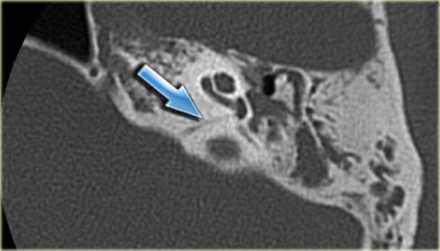

2. КТ при интралабиринтной шванноме:

• КТ без КУ:

о Обычно норма, ИЛШ не видна

• КТ с КУ:

о ИЛШ не видна даже на тонкосрезовой КТ с КУ

• КТ в костном окне:

о Норма, за исключением случаев, когда опухоль пролабирует в среднее ухо через нишу круглого окна

о При очень больших опухолях (трансмодиолярных, трансмакулярных, трансотических) могут обнаруживаться костные эрозии

о КТ в костном окне обычно не позволяет сделать заключение об ИЛШ